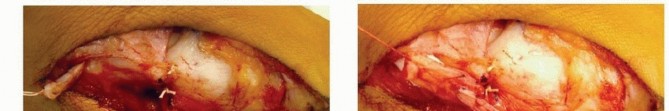

Medial Soft Tissue PlicationPlicate the talonavicular joint capsule plantar medially but not dorsally ( TECH FIG 5A).

---

TECH FIG 5 • A. The plantar and medial aspects of the talonavicular joint capsule are repaired side to side with large-gauge dissolving suture material; the redundant capsule has already been resected. B,C. The proximal slip of the tibialis posterior is advanced distally through a slit in the distal stump of the tendon and repaired with large-gauge dissolving sutures. (From Mosca VS. Calcaneal lengthening osteotomy for valgus deformity of the hindfoot. In: Tolo V, Skaggs D, eds. Master Techniques in Orthopaedic Surgery: Pediatric Orthopaedics. Philadelphia: Lippincott Williams & Wilkins, 2008:263-276.)Advance the proximal slip of the tibialis posterior tendon about 5 to 7 mm through a slit in the distal stump of the tendon. Repair this Pulvertaft weave with an absorbable suture material ( TECH FIG 5B,C).